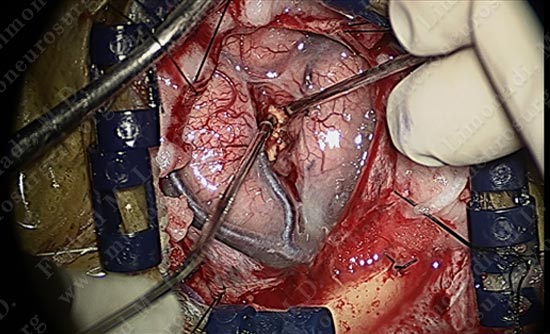

The tumor is nicely dissected out as patient is talking to the surgeon and being examined by the surgical team.

Tumor is removed without any injury to the motor cortex or adjacent neuro-vascular structures. Patient is awake and doing well with no neurological deficit.